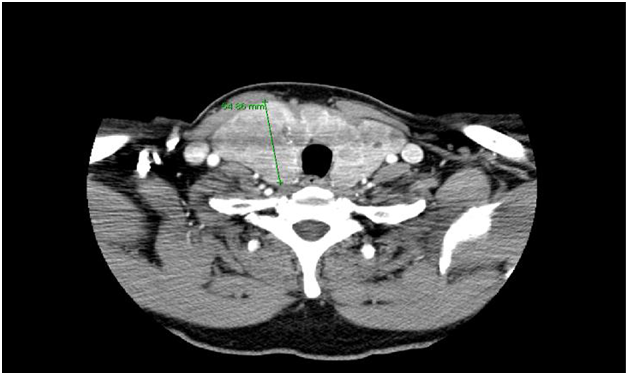

Upon further questioning it was found that the patient’s symptoms were always precipitated by turning his head to the right side…!! “When he was on vacation the spells occurred while he was looking out the window to the right; whereas at home after running up stairs there was a sharp right turn.” Therefore there was a high suspicion that a neck mass is compressing the carotid sinus causing a reflex bradycardia. Consequently a CT neck was performed that revealed a large goiter compressing on adjacent structures including the right carotid sinus (Figure 3 & 4).

Figure 4 Asymmetric large goiter confirmed by CT scan of the neck.